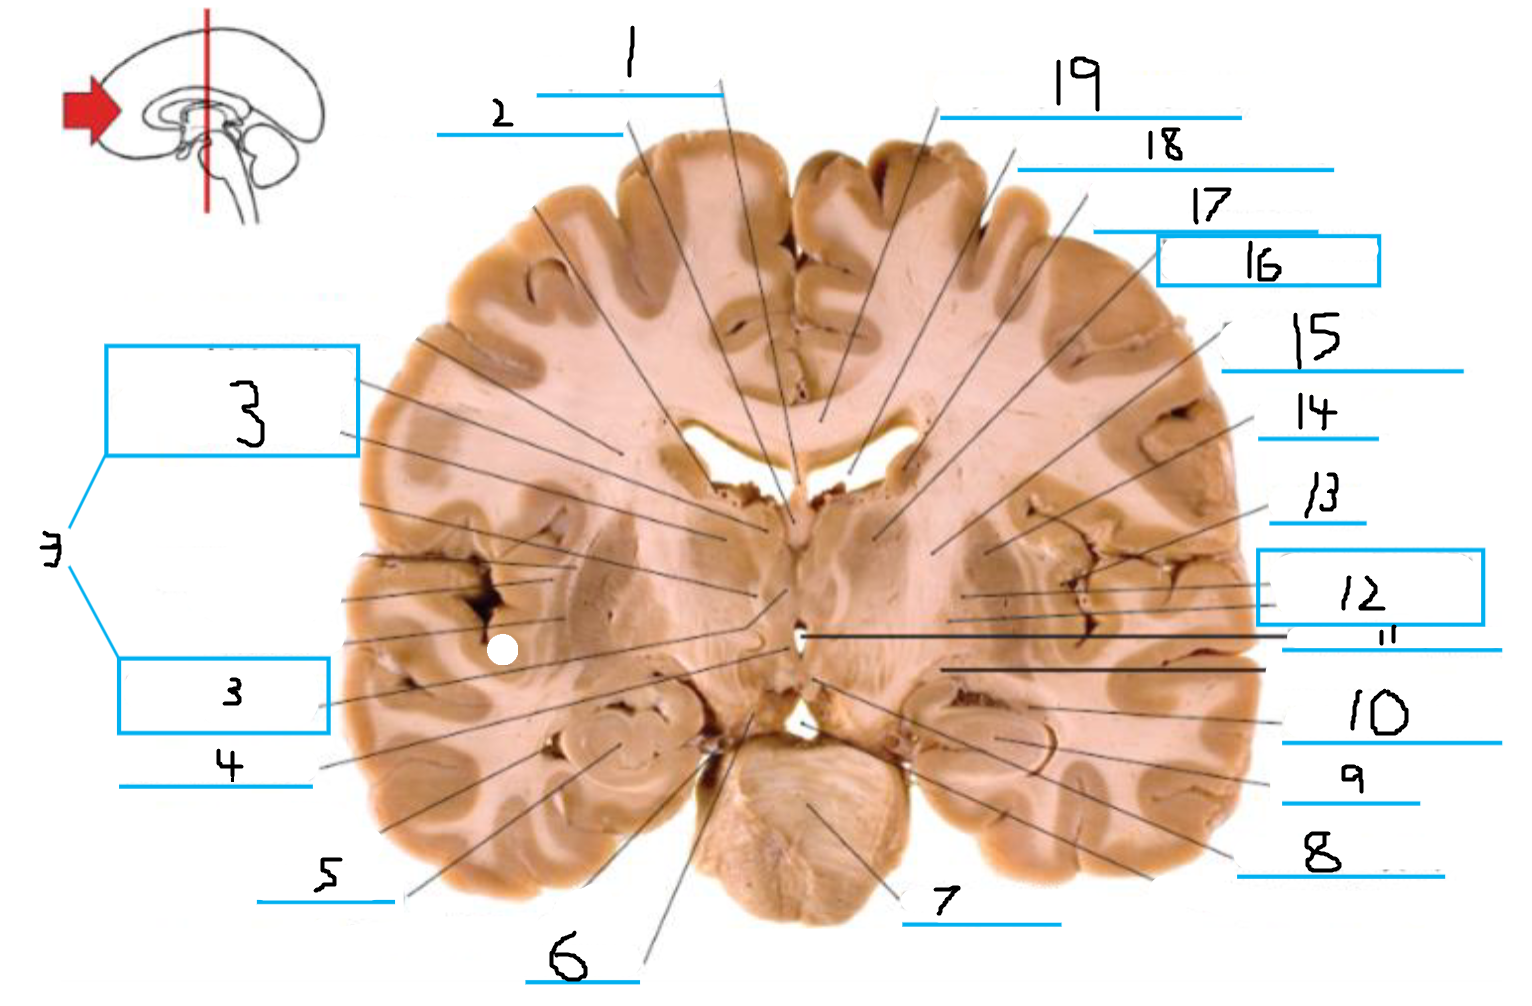

#3 and #16 are the:

Thalamus

#4 is the:

Hypothalamus

#5 and #9 is the:

Hippocampus

#6 is the:

Crus Cerebri

#7 is the:

Basilar Pons

#8 is the:

Mammillary Body

#10 is the:

Caudate

#11 is the:

Third Ventricle

#12 is the:

Globus Pallidus

#13 is the:

Insula

#14 is the

Putamen

#15 is the:

Internal Capsule

#17 is the:

#18 is the:

Lateral Ventricle

#19 is the:

Corpus Callosum